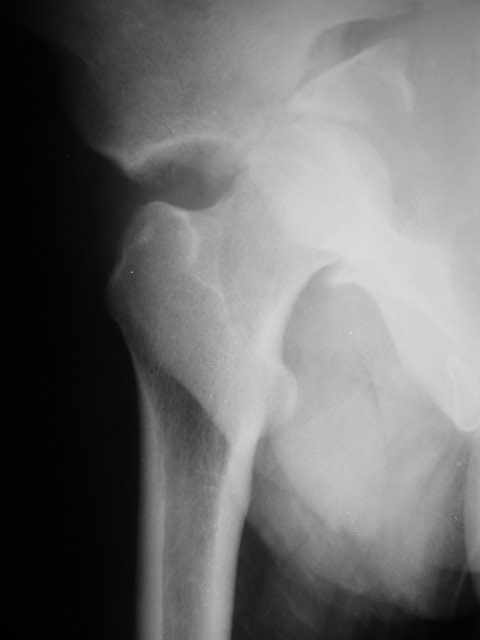

Уважаемые коллеги!Молоодой человек 20 лет,задний вывих правого бедра, поперечный перелом и перелом заднего края правой вертлужной впадины. Самое сложное то, что после травмы уже прошло 8 недель. Планируем ввыполнить остеосинтез из двух доступов (задне-боковой и подвздошно-бедренный). Если у кого есть опыт остеосинтеза впадины из двух доступов посоветуйте с какого лучше начинать в данной ситуации. Алексей.

Какой доступ вам более известен, но для совета нам надо определится с переломом, на половине обтуратор косой проекции не все элементы видны.

Есть ли другие снимки, пришлите на сайд-прямой таз, две косых: обтуратор и подвздошный Judet views, затем можно поговорить о доступе.

Все тебе два доступа сделать хочется, а зачем неясно. Снимки обрезанные, видно огромный фрагмент заднего края. Он повидимому и является ключем стабильности. Если перелом передней колонны низкий, на него можно не обращать внимание, так что возможен вариант восстановления только задней колонны из задне-бокового доступа, даже без остеотомии вертела. Особое внимание на сохранение питания отломка.

Пришли все-таки нормальные снимки, тогда может быть станет понятны твои проблемы, зачем тебе изнутри забираться, пока это очень и очень сомнительно.

Послал все снимки но видимо не все дошли. досылаю

Подвздошная

Вот что получилось (снимок операционный, качество не очень). Первый доступ был подвздошно-бедренный из которого разделили почти весь поперечный перелом, затем из задннего вправили вивих, выделили задний край и зафиксировали винтом.